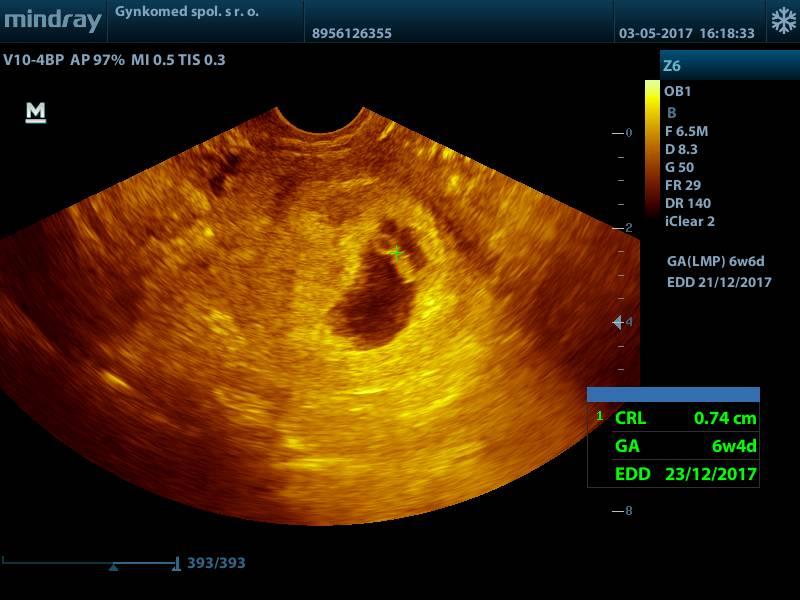

@luta13 Ďakujem zlatíčko :-* Veľmi som sa potešila keď doktor len pozrel a hneď hovorí, že ako krásne už bije ❤

@nikuskaniki ja mam podobnu fotku - tiez je vidiet malicke babätko a placentu (akoby kruzok dole pod babätkom - to je placenta), no Ty si 6tt.+4, ja som bola vtedy az 8tt.+1...Kuk foto 😇

@nikuskaniki jeeeej nádherne babatko mojko..Dúfam že aj my dopadneme napodobne 😉áno dnes sme na rade a už sa budím či nezaspim 😝Tak pekne tehulkujte mojko a vážne zatiaľ máš termín 23.12. Budeme si písať s pôrodnice 😝